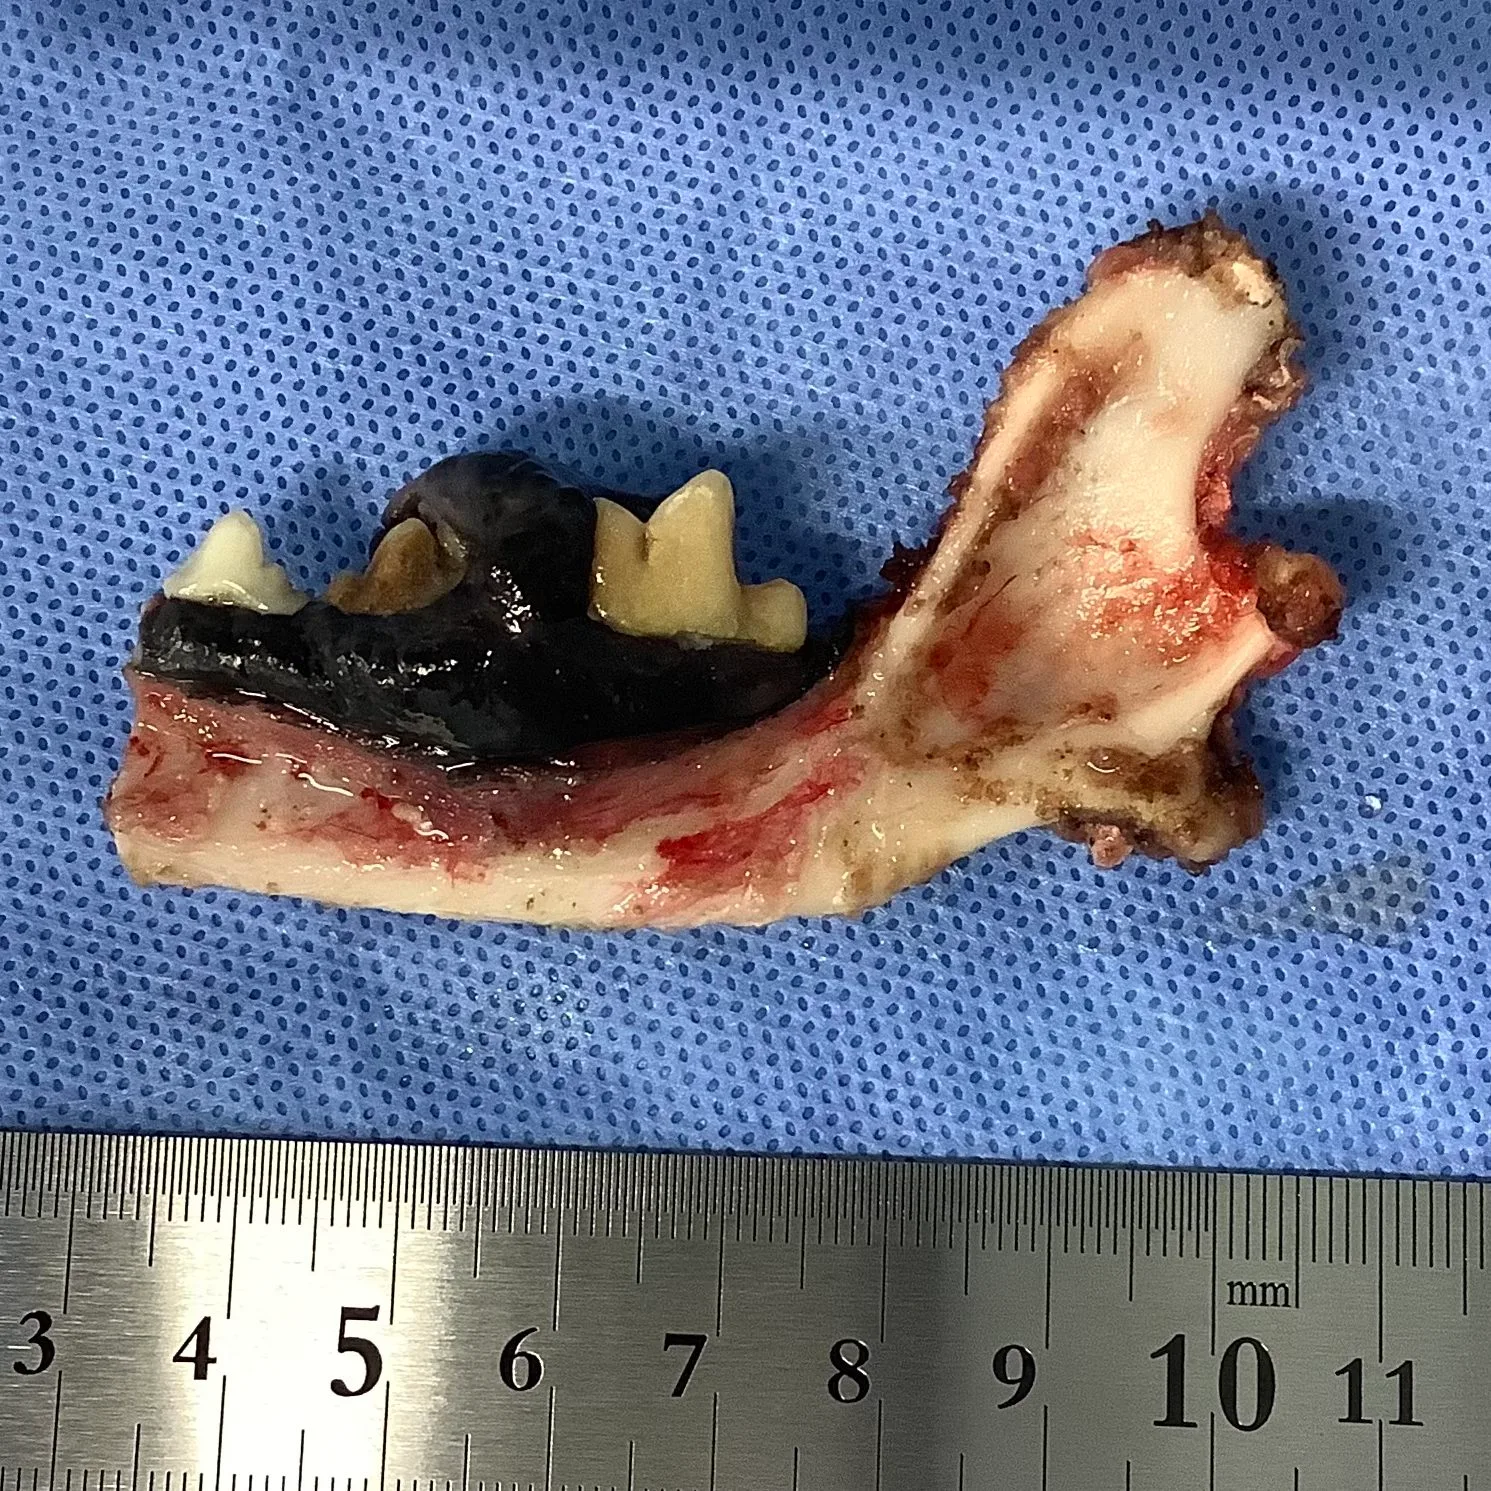

外科治療

第一選択となる治療です。

広範囲での切除(顎骨を含んだ)が推奨されます。

ステージングのためにリンパ節も同時に摘出します。

※クリックするとモザイクなしで表示されます。

*画像提供:松原動物病院